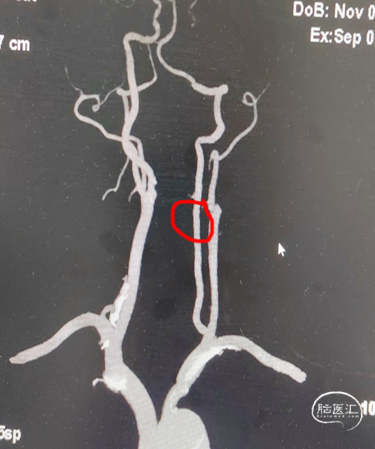

· 于我院查颈部血管超声示“双侧颈动脉内-中膜增厚伴多发斑块形成;左侧颈内动脉闭塞可能,建议超声造影;左侧颈外动脉起始处狭窄,狭窄率70-99%;右侧锁骨下动脉起始处斑块形成”。查头颈部血管CTA示“主动脉弓及弓上大血管动脉粥样硬化表现,左侧颈内动脉颈段至破裂孔段闭塞;左侧锁骨下动脉起始部中重度狭窄”。

头颈部CTA影像及报告(2024-07-24)。

入院头颈部CTA影像及报告(2024-09-05)。